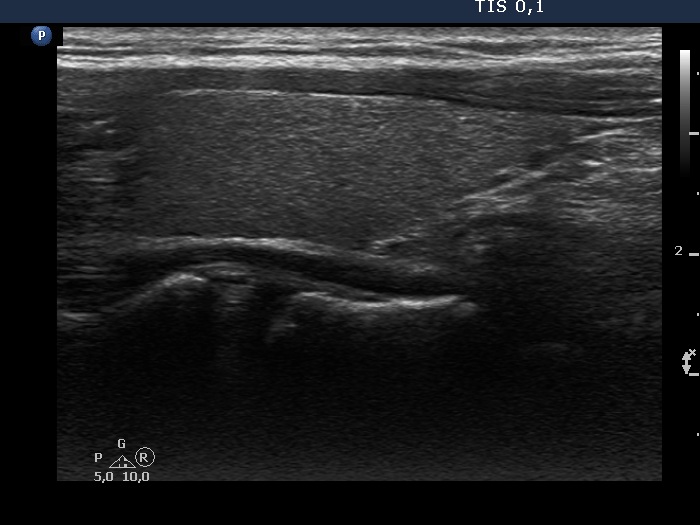

Study on 100 consecutive patients with thyroid nodule - case 023 (ultrasonographic picture 5)

Left lobe, longitudinal scan.